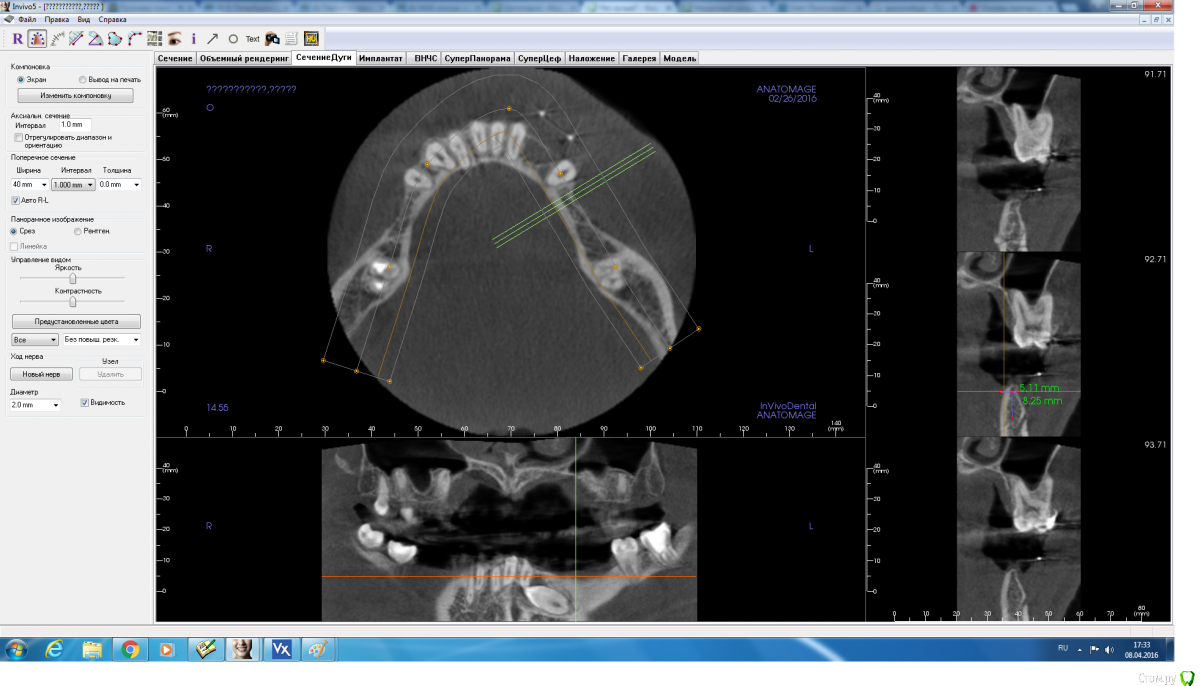

adamskot Опубликовано 8 апреля, 2016 Поделиться Опубликовано 8 апреля, 2016 Коллеги, доброго времени суток.Ретенированный клык уже удален,на его место биоосс и мембрана.Кто как бы поступил в третьем сегменте? заранее спасибо за мнения) Ссылка на комментарий

red_butler Опубликовано 8 апреля, 2016 Поделиться Опубликовано 8 апреля, 2016 срезы выставлены не корректно 2 Ссылка на комментарий

adamskot Опубликовано 8 апреля, 2016 Автор Поделиться Опубликовано 8 апреля, 2016 Момент, сейчас поправлюТак? Ссылка на комментарий